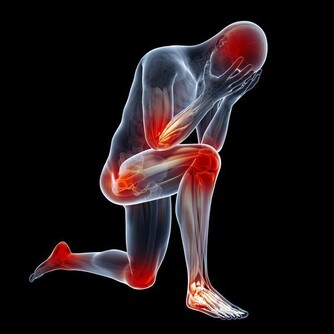

8.易疲憊,肌肉無力、酸疼

不管是甲狀腺功能減退症還是甲狀腺功能亢進症,都會引起疲憊感,讓你的身體變得很虛弱。不正常的身體機能,會打破身體的能量平衡,使身體感到疲憊。即使是沒有進行劇烈運動,也會出現關節僵硬、肌肉酸疼、無力的症狀,有時候還會感覺大腦遲鈍、頭腦不清醒。